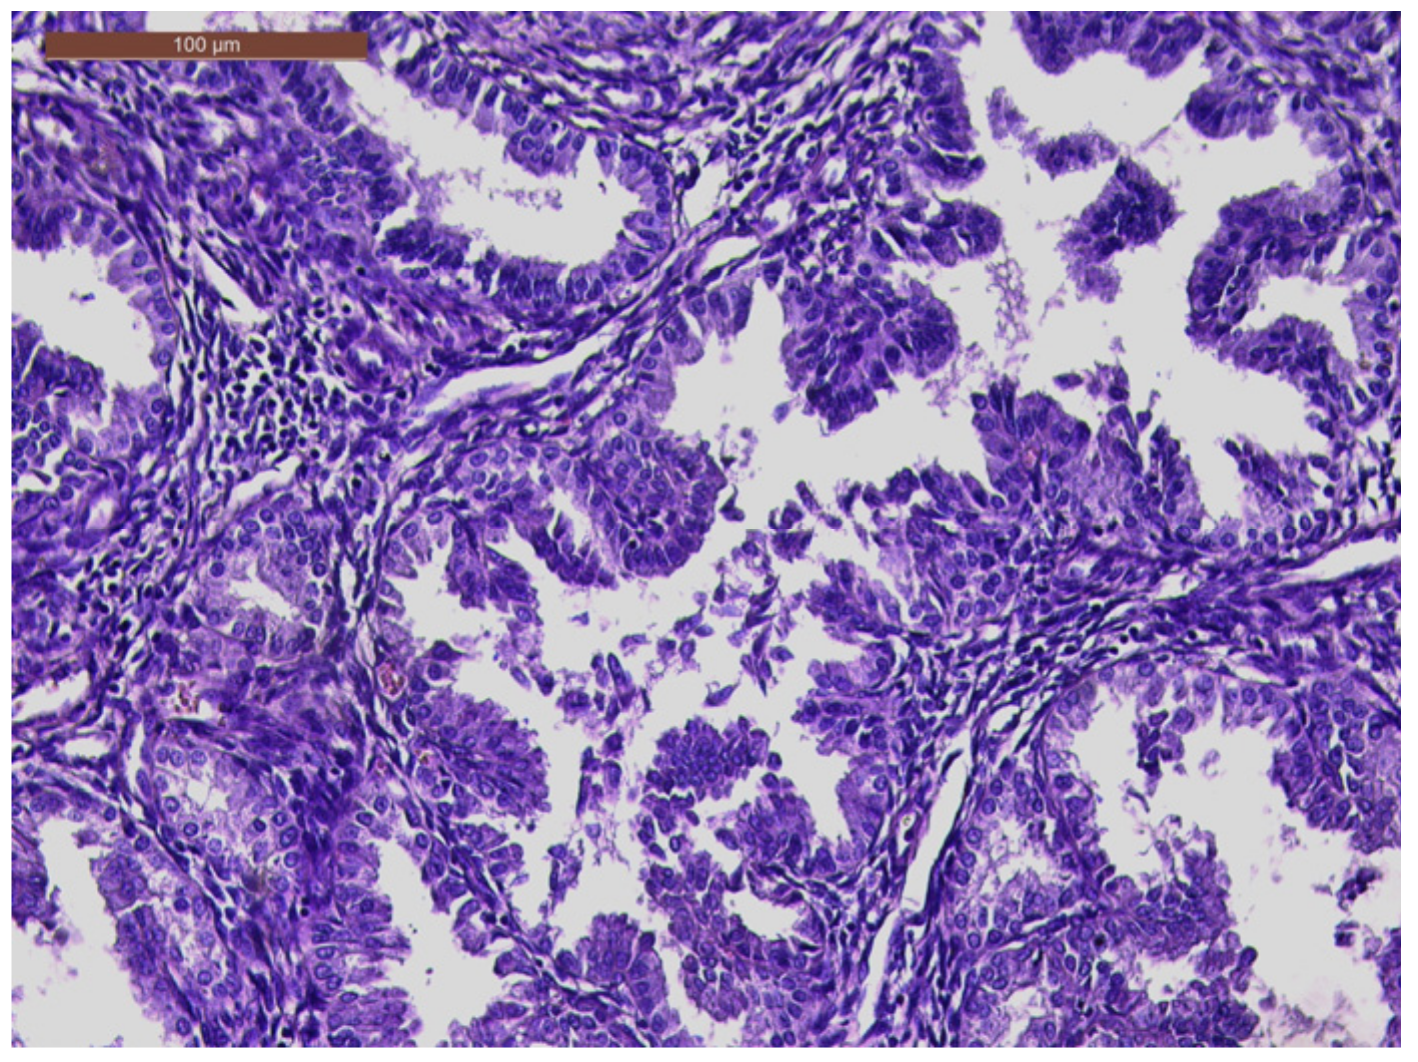

The histopathological exam revealed the tissue fragments to be sufficiently delimited by a thin layer of the endometrium composed of a biphasic stromal and glandular proliferation and represented by cellular stroma with edematous areas with thin blood vessels interspersed with thick bundles of smooth muscular fibers that included irregularly contoured secretory endometrial glands (Figure 4 and Figure 5), organized in hyperplastic lobular areas, and lined by the simple and pseudostratified epithelium with hyperchromatic nuclei (Figure 6), eosinophilic metaplasia, and a tendency for squamous differentiation.

Our microscopic findings are consistent with the following histopathological characteristics that define the atypical polypoid adenomyoma: a well-circumscribed biphasic tumor composed of endometrioid glands with a complex or lobular histoarchitecture, squamous morular metaplasia, and sometimes cytologic atypia, interspersed with a fibromyomatous stroma, which may present myxoid change.

Figure 6. Hyperplastic endometrial glands, with irregular lumen; focal pseudostratified epithelium; and hyperchromatic nuclei (HE × 20).